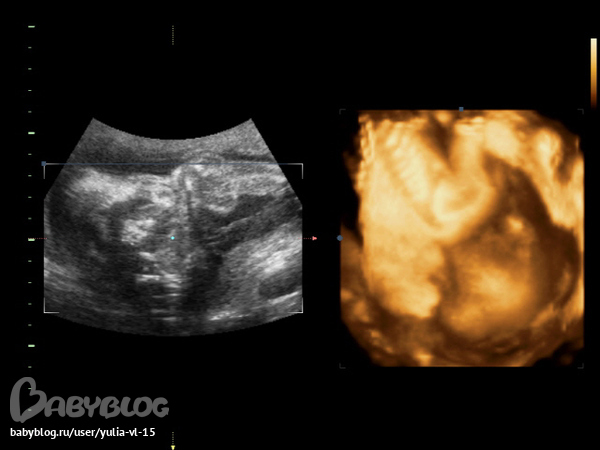

А вот здесь видно как Саша голову ручками прикрывает)) Вообще он оочень не любил разные УЗИ, Допплеры и всё такое))